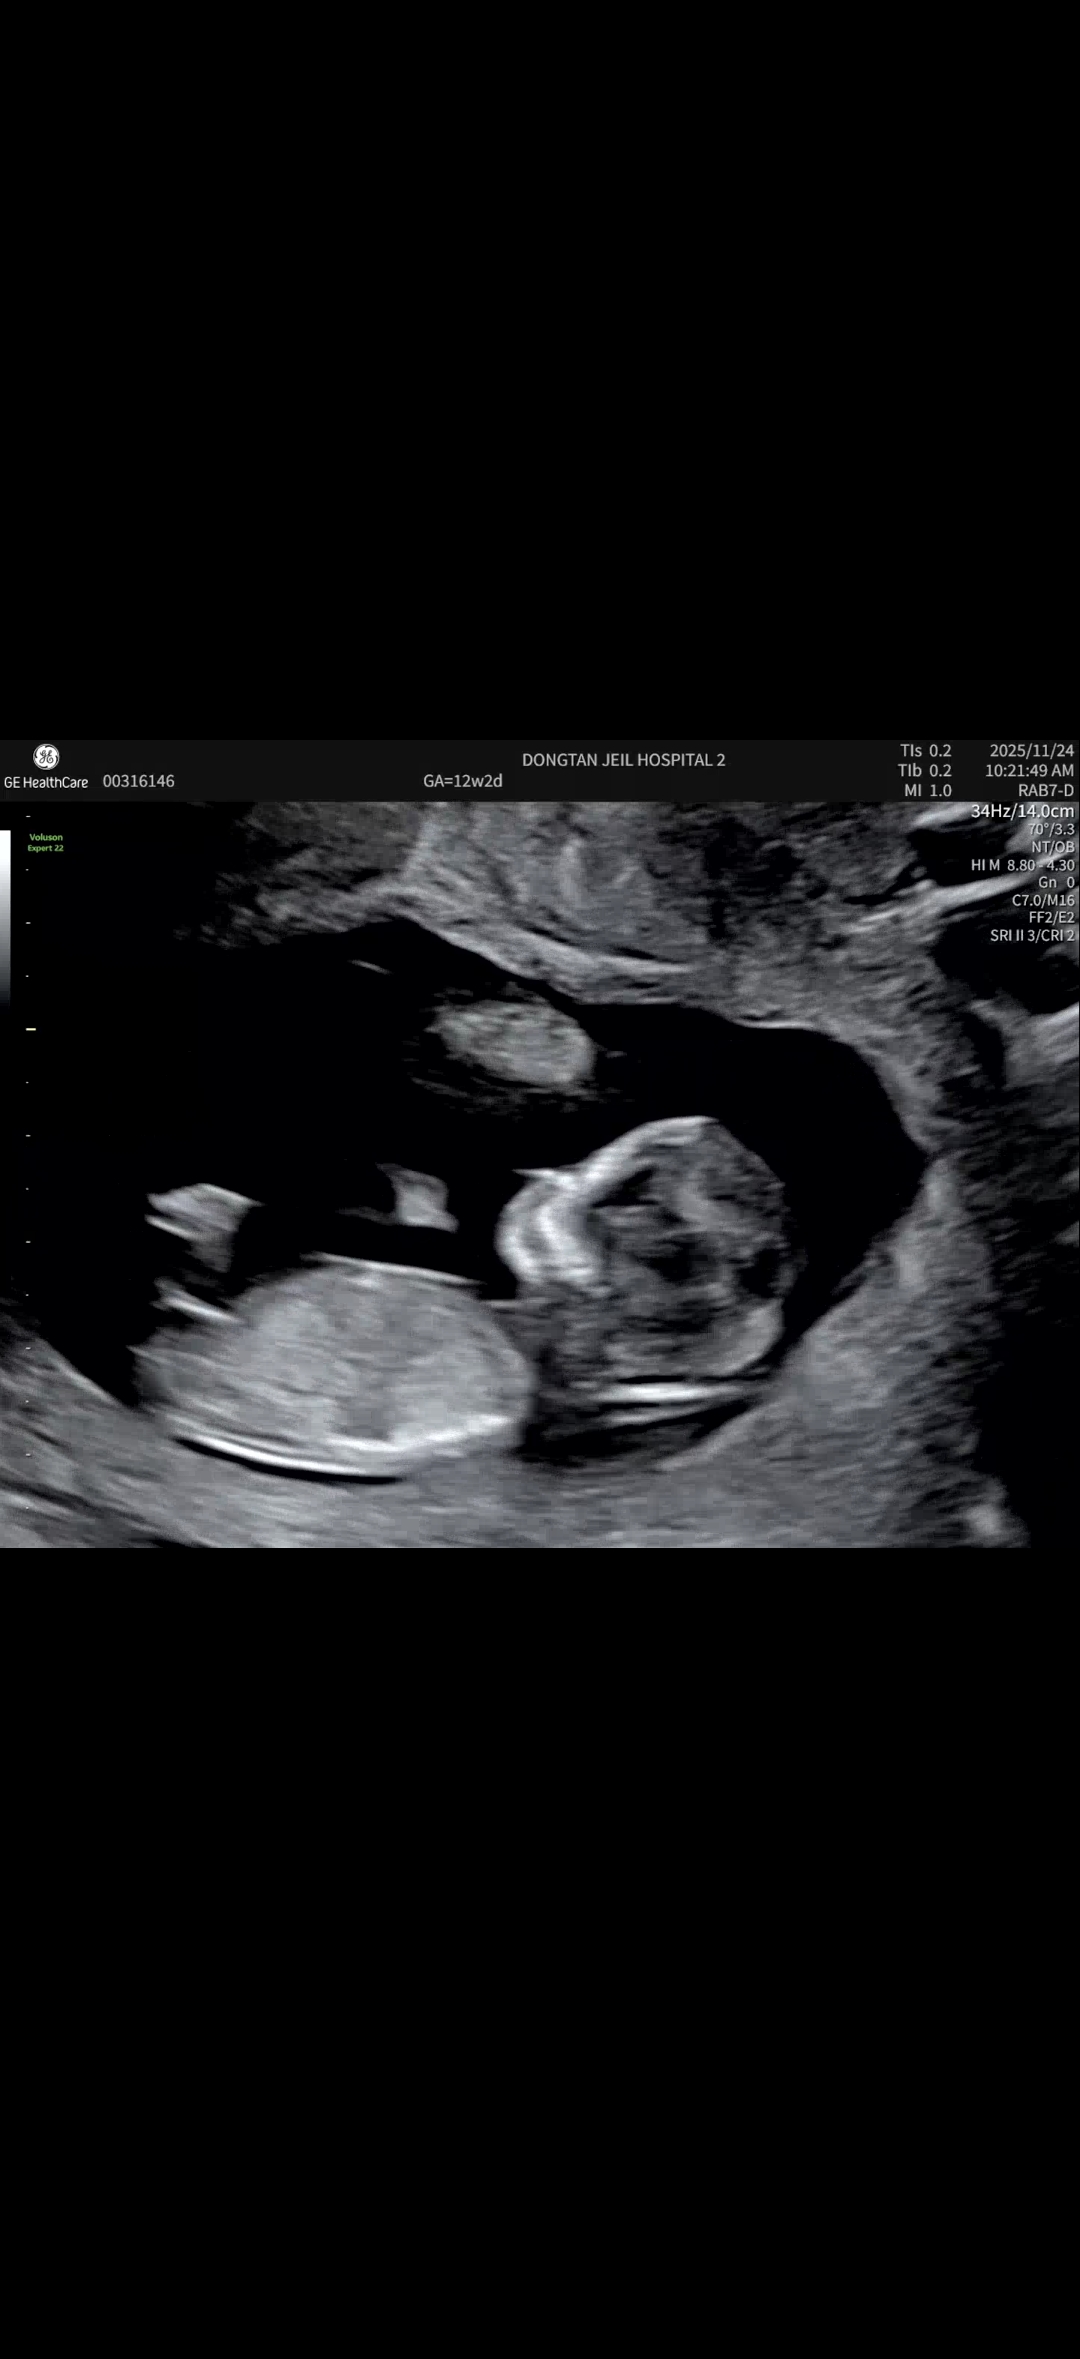

12주2일 초음파 각도법 궁금해요~

12주2일차 각도법 성별 궁금해요~